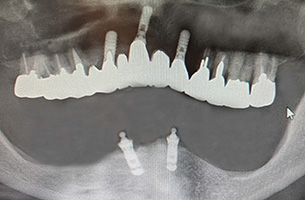

30年経過症例 / 92歳(2025年現在)・男性

1995年 上顎インプラント埋入時(61歳)

2002年 下顎インプラント埋入時(69歳)

92歳(2025年現在):シッカリ噛める事で咀嚼筋・表情筋が鍛えられ顔に張りがあり高齢にも拘らず縦ジワが全く見られません。最近まで車の運転をされていました。